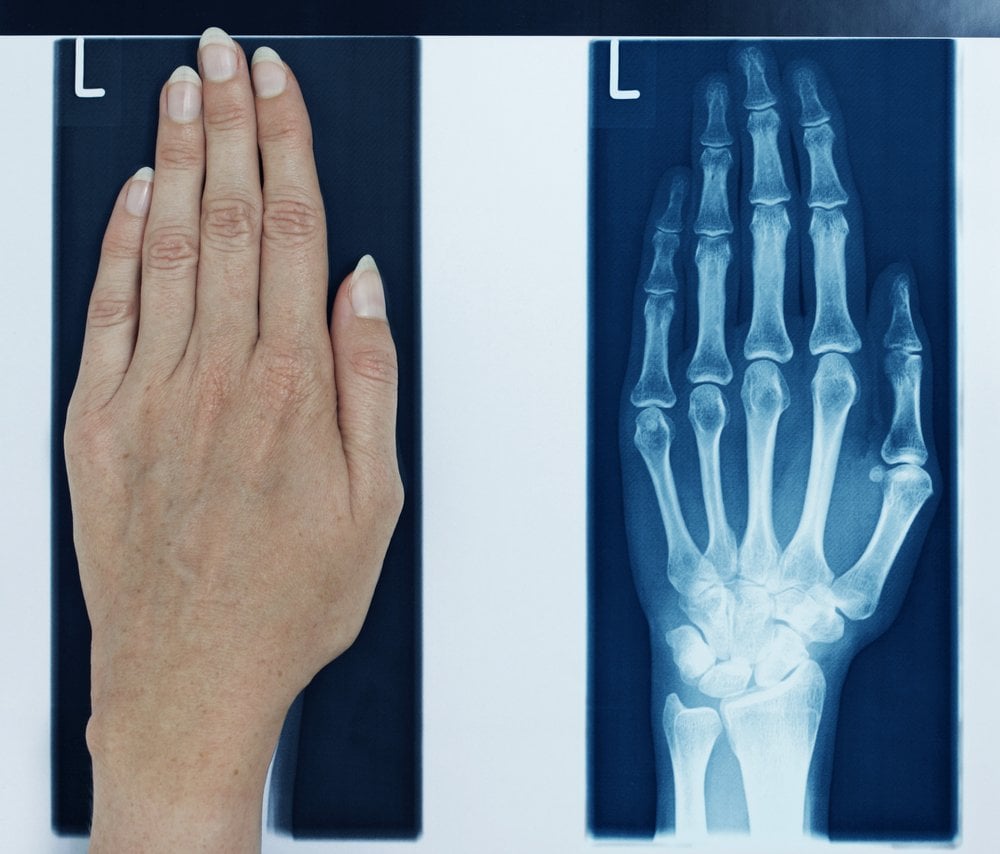

Thanks to movies and pop culture’s love for X-ray vision, we have been led to believe that X-ray vision will let us see through other people’s clothes – as well as buildings and underground bunkers. The truth is, even if you could see through someone’s clothes using your X-ray vision (which, by the way, you can), it’s only their bones that you would be able to see. X-rays have a very small wavelength and high amounts of energy, which is why they can penetrate a lot of stuff to give that ‘see-through’ vision effect.